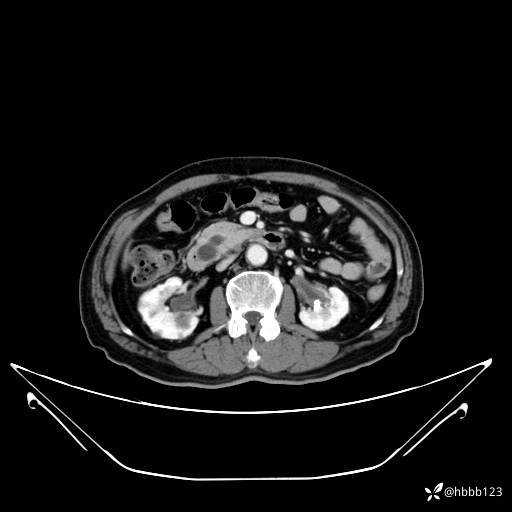

延迟期: